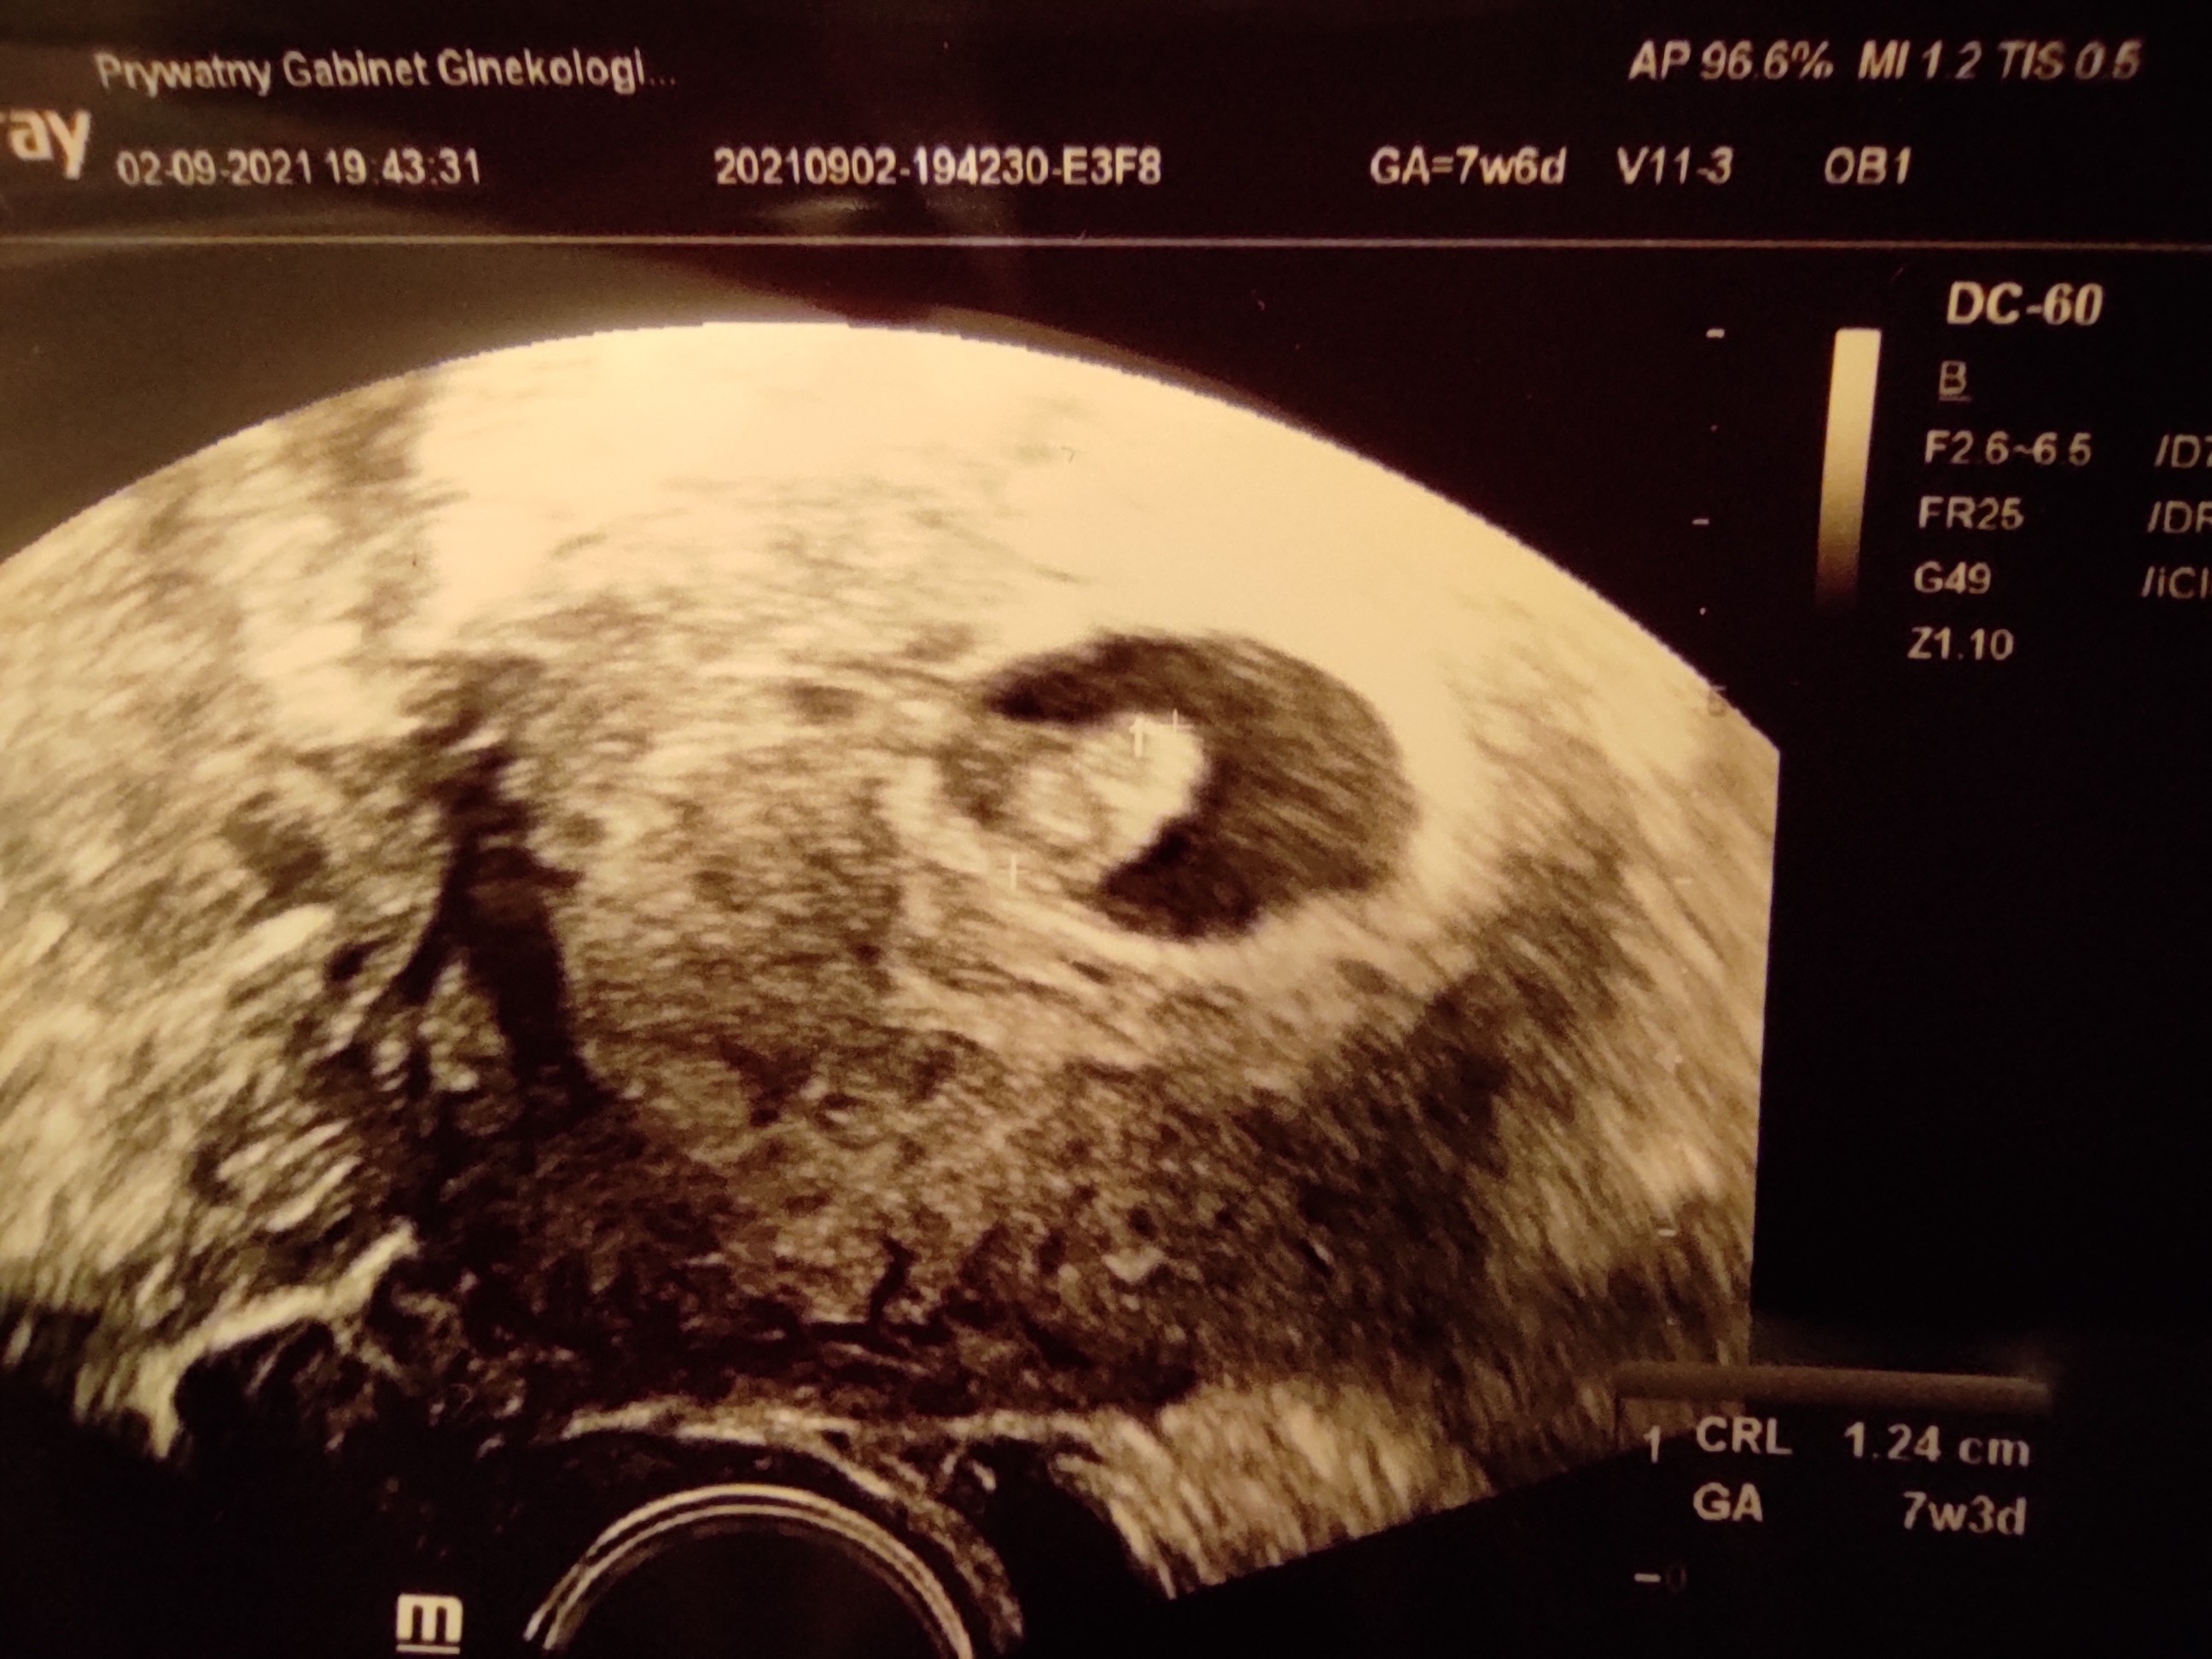

Ja już po wizycie, jest serduszko

Lekarz miał mega słaby sprzęt, ale na pewno było widać zarówno zarodek jak i migające serduszko